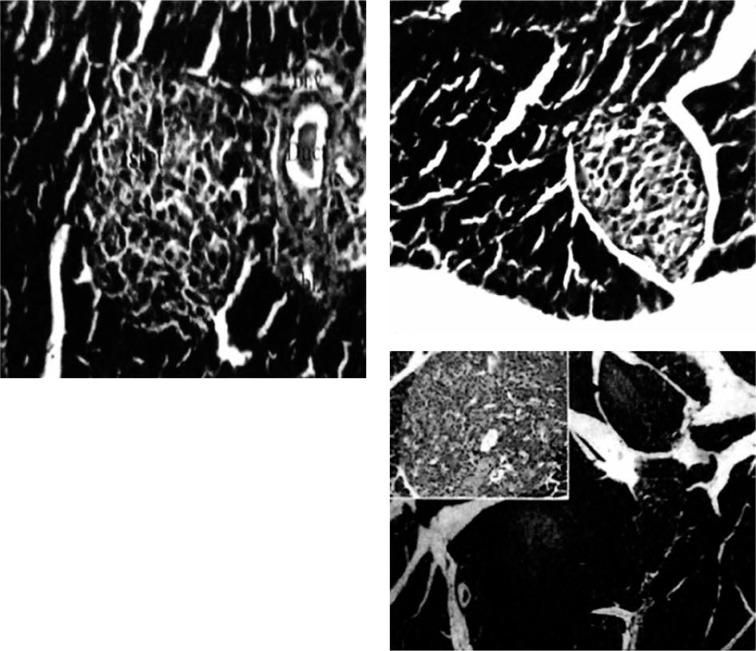

We used novel formulations of low-dose IL-2 loaded on chitosan nanoparticles. The study included 116 T1D BALB/c mice experimentally induced by streptozotocin, divided into groups. Their splenocytes were maintained in a short-term culture for assessment of expression of CD4+FOXP3+ Treg and NKp46+NK by both flow cytometry and enzyme-linked immunoassay (ELISA). Morphological, immunohistochemical, and morphometrical analyses were done. suppressor assay was used to assess the suppressor effect of Treg cells after exogenous IL-2 treatment.

我们使用了负载在壳聚糖纳米颗粒上的低剂量IL-2的新型制剂。该研究包括116只经链脲佐菌素实验诱导的T1D BALB/c小鼠,分为几组。通过流式细胞术和酶联免疫吸附测定(ELISA)对它们的脾细胞进行短期培养,以评估CD4+FOXP3+ Treg细胞和NKp46+NK细胞的表达。进行了形态学、免疫组织化学和形态计量学分析。采用抑制试验评估外源性IL-2处理后Treg细胞的抑制作用。